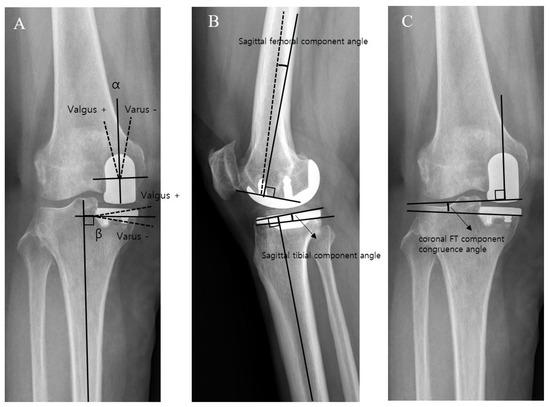

4. Clinical and Radiological Assessment

| Coronal femoral component angle (α) (°) | 2.4 ± 4.9 | −1.1 ± 3.2 | <0.001 |

| Coronal tibial component angle (β) (°) | −1.0 ± 4.3 | −3.0 ± 2.4 | 0.001 |

| Sagittal femoral component angle (°) | 3.1 ± 8.7 | 5.0 ± 4.1 | n.s |

| Sagittal tibial component angle (°) | 7.2 ± 3.5 | 8.2 ± 2.7 | n.s |

| Coronal FT component congruence angle (°) | 3.4 ± 4.5 | 1.9 ± 2.6 | 0.028 |